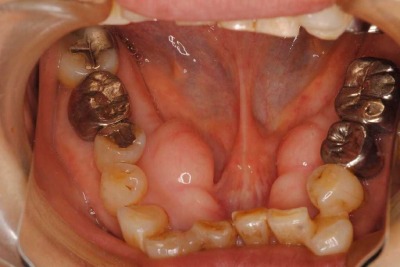

この方は年齢と共に前歯が重なってきて他医院では「加齢によるもので、どうしようもない」と言われて当医院を受診されました。

実は、人の歯は年齢と共に奥歯が前に倒れてきて、前歯は重なるものなのです。

左下前歯の重なりが無くなって、きれいになったので、右も新しく装置を入れてほぼきれいに一列になってきました。